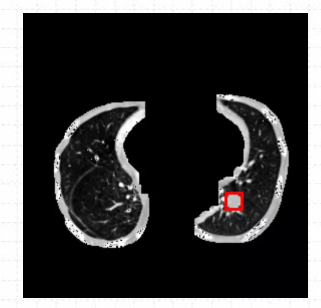

2.1准备数据

关于医疗图像肺结节病灶数据的话,这里本文是利用官方肺结节检测数据集

LUng Nodule Analysis 2016(LUNA16)

进行处理后得到的,已经自己人为标注好了300张病灶数据,可以直接导入华为云ModelArts AI开发平台进行使用。

关于整个肺结节检测数据集的话,数据集文件的大小不大,有35M,共300张已标注好肺结节病灶的文件。